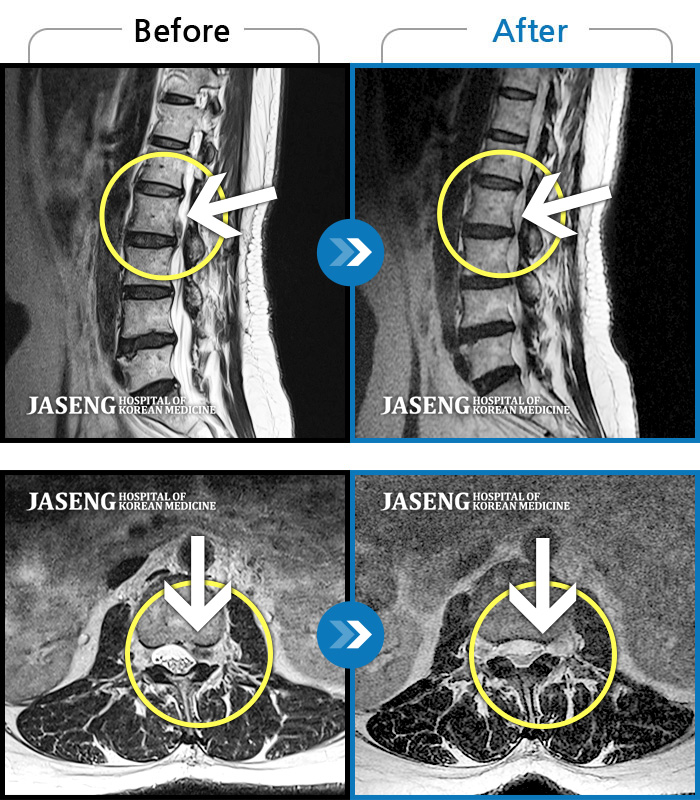

ȯںп Ǹ ǿ ԿǾ, ο ġ ۿ Ƿ ġḦ Ͻñ ٶϴ.